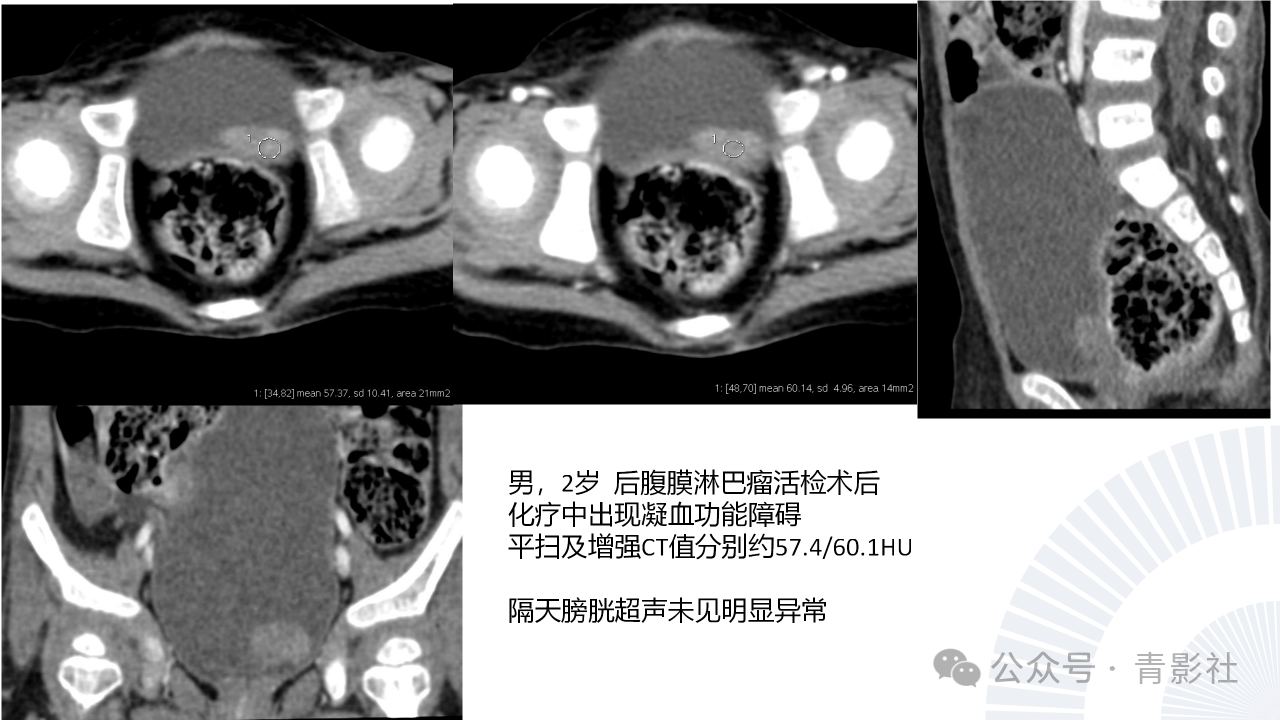

儿童膀胱肿瘤诊断要点及陷阱